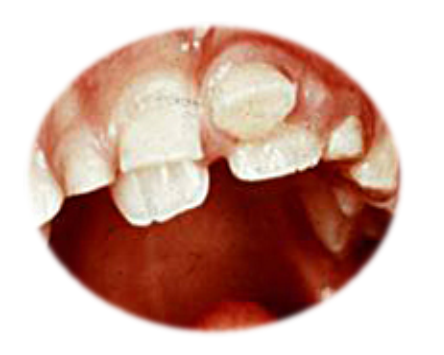

Nepravilno nicanje donjih stalnih sekutića je posledica velikih zuba i uskih vilica i znak su poremačaja u postavi zuba koji se naziva teskoba.(Slika 1B)

Slika 1. Napravilno nicanje donjih stalnih sekutića iza mlečnih predhodnika(A) često je znak da nema dovoljno mesta u vlilicama(veliki zubi, male vilice) i da može da nastane nepravilnost u postavci koja se naziva teskoba(B)

Čim se primeti da se stalni zubi pojavljuju iza mlečnih sekutiča, koji su minimalno rasklaćeni, potrebno je da se hitno javite dečjem stomatologu.(slika 1A) Neophodna je procena veličine stalnih zuba i postojećeg prostora i na osnovu toga odlučuje da li da se mlečni prvi sekutići odmah izvade, ali često i drugi, ili da se sačeka još malo. Značajno je i da li su mlečni zubi počeli da se klate ili ne. Sledi će najverovatnije i nošenje proteze za ispravljanje zuba(ortodontski aparat), koje imaju za cilj da prošire vilicu i obezbede prostor za smestaj zuba. Ako se na vreme reaguje i podstiče rast vilica moće da se izbegne(ali ne uvek) složenija terapija. Ako se zakasni(to znači više godina) i nista ne preduzme, dok se ne postave i bočni stalni zub, često je jedino rešenje vađenje zdravih stalnih zuba(najčešće prvi premolar ili popularno “stalna četvorka”) kako bi se obezbedio prostor za smeštaj svih zuba.